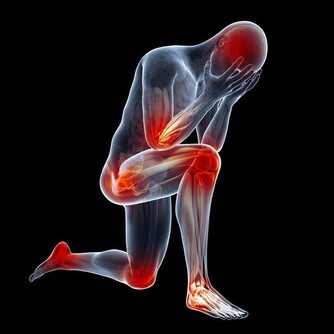

常常食用可以刺激身體排毒,應對由於身體毒素累積所造成的疾病,

如風濕、關節炎等。另外,芹菜還可以調節體內水分的平衡,改善睡眠。